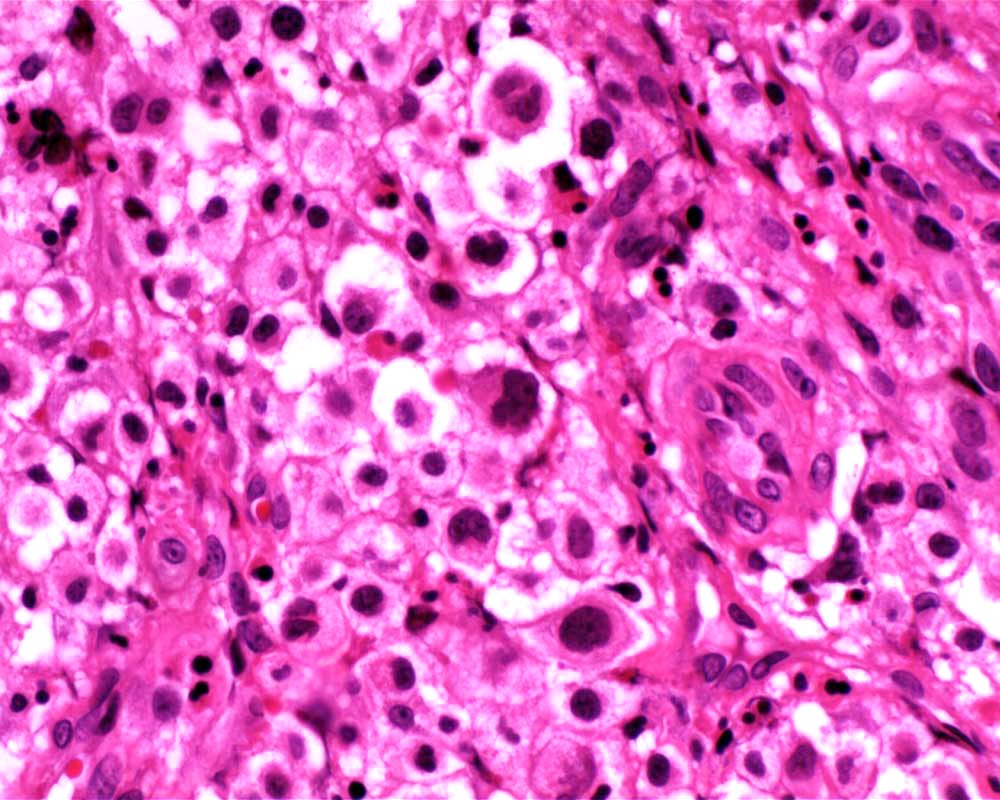

Case: FemurLesion

Final Diagnosis: